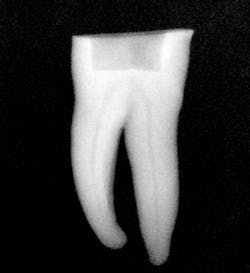

Figure 1: Radiograph of extracted tooth to demonstrate preoperative canals.

After preparing straight-line access to the canal orifice (figure 1), explore the canal using small-sized instruments. I typically use a size 08 SafeSider by hand with the help of an apex locator to determine working length. I then use the SafeSiders in sizes 10, 15, and 20 to verify patency and confirm a smooth, reproducible glide path (figure 2). I always irrigate and enlarge the glide path to a minimum 20/02 preparation.